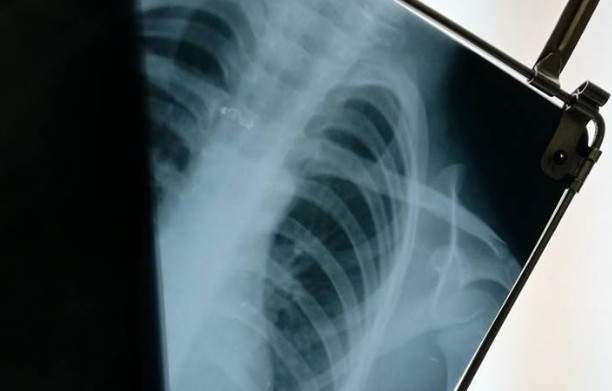

Он рассказал, что предмет был серого цвета, примерно 2-3 сантиметра в длину и он застрял у него чуть ниже шеи. Диагностика в больнице и рентген действительно указали на наличие инородного предмета в пищеводе.

«Врач срочно ведет нас делать функциональную эндоскопию и предупреждает: существует вероятность, что инородное тело опустится по пищеводу, когда ребенок будет вдыхать газ для общего наркоза. Ребенка подвергают общему наркозу. Проводят эндоскопию. Эндоскопия не проявляет следы инородного тела в пищеводе», — пересказал Всеволод Некрасов.

Спустя несколько дней, 22 сентября, хирург из «Охматдета» подтвердил, что на первом рентгене видно инородное тело. Однако после того, как снимки переделали, оно перестало просматриваться. Видимая угроза для здоровья ребенка миновала, однако, по словам родителя, в саду не пытались выяснить причину происшествия или поинтересоваться состоянием воспитанника.